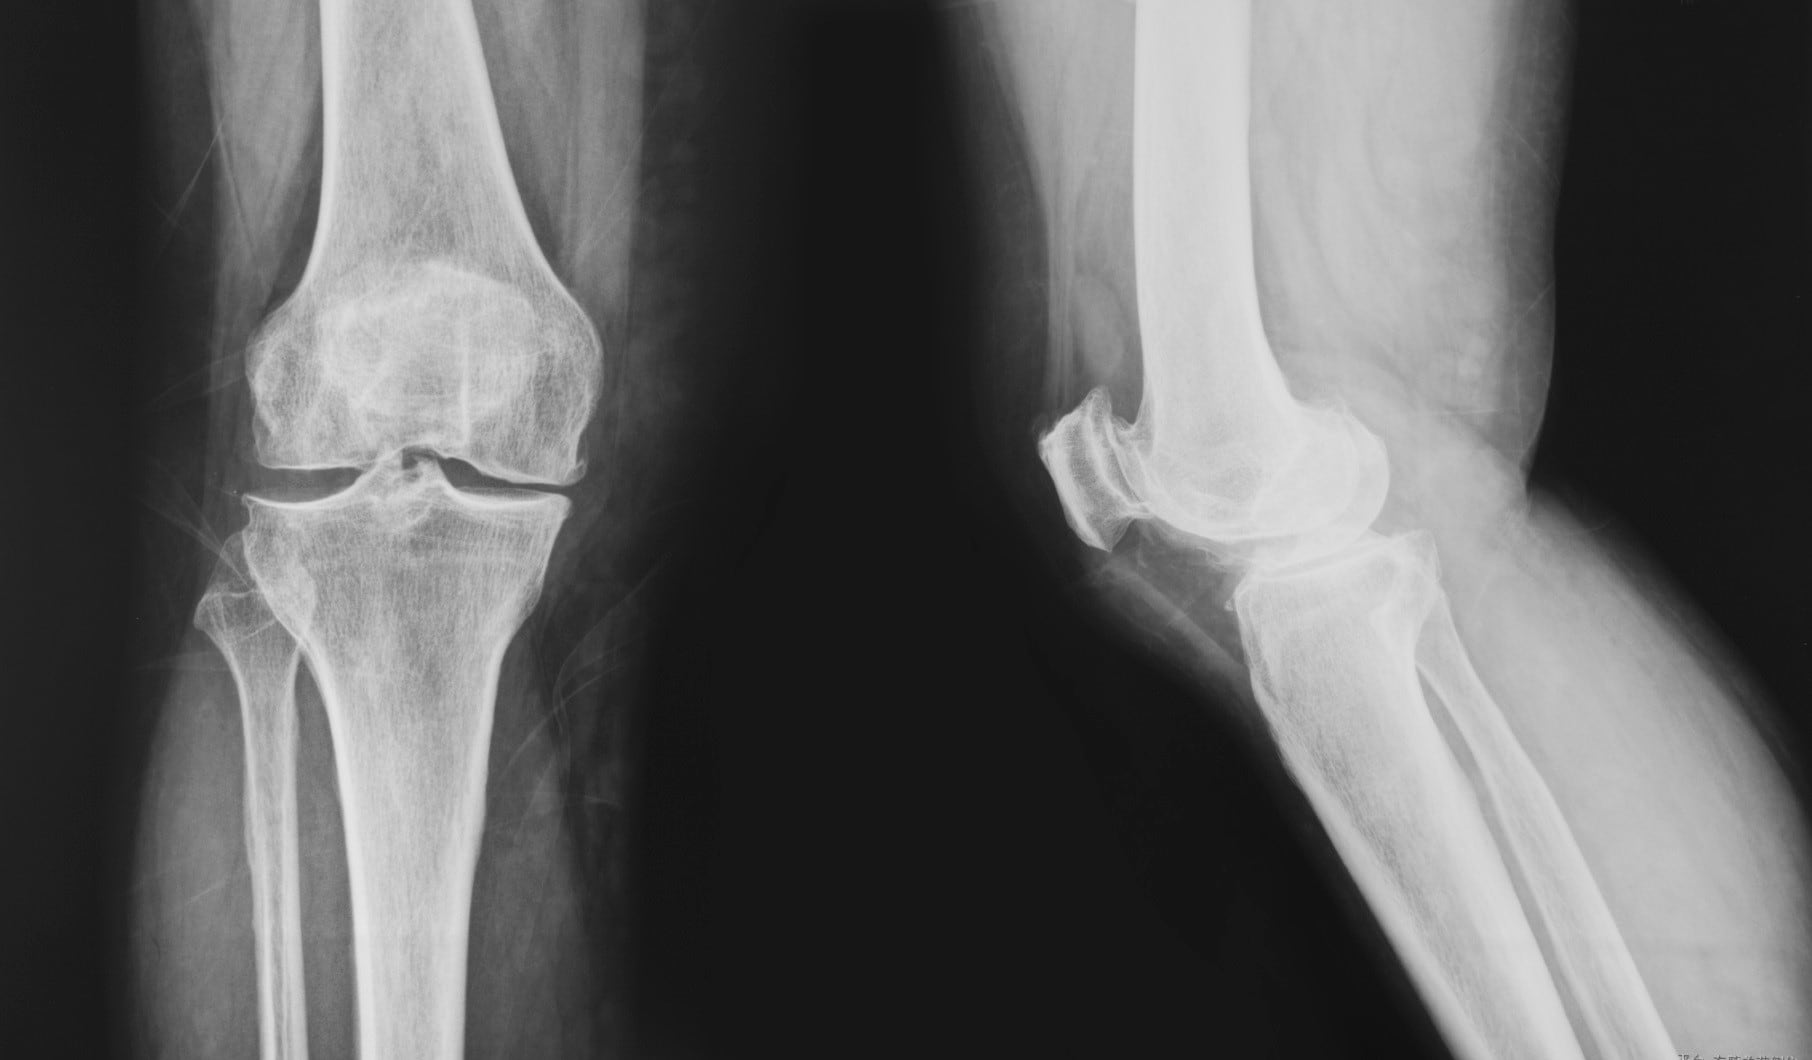

Glucosamine has, along with chondroitin, been the old standby ingredients in this category for decades. Quality issues, competition from new ingredients and questions about efficacy of glucosamine have eroded sales, experts say. The global retail value of glucosamine products was valued at $1.895 billion in 2009, which then grew to $2.041 billion in 2011, according to data from Euromonitor International*. But then the market began to flag, with 2013’s value at $1.823 billion, and the 2015 forecast predicting a market worth $1.770 billion. While there may be a decline in the overall glucosamine market, one sector that is growing is in vegetable-sourced glucosamine, said Cal Bewicke, CEO of Ethical Naturals, which supplies a vegetable-derived non-GMO glucosamine called GreenGrown.

Efficacy, quality and smaller dosage sizes are helping suppliers of collagen ingredients gain traction in the joint health marketplace. But suppliers agree that their ingredients occupy the thin edge of the wedge, and that commodity glucosamine and chondroitin supplements still predominate.

Omega-3s are one well know ingredient that has had little success in breaking into the joint health market in a big way. Harry Rice, PhD, chief science officer for GOED, said this has to do with the bifurcated nature of the market, dealing as it does with both osteoarthritis and rheumatoid arthritis. The data for omega-3s in osteoarthritis looks promising, Rice said, but for rheumatoid arthritis, “The data is just not good,” he said.